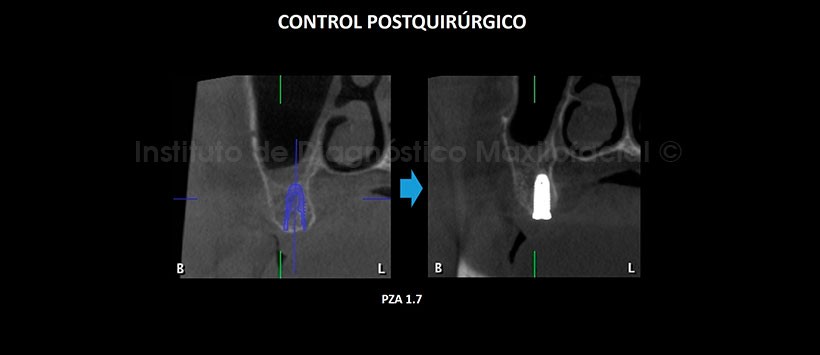

En la tomografía computarizada de haz cónico (TCHC), se realiza la planificación virtual de colocación de cuatro implantes dentales en zonas de piezas 17, 23, 26 y 27 (Figura 2, 3), y sobre la planificación se realiza la confección virtual de la guía quirúrgica (Figura 4). En la reconstrucción 3D (Figuras 5) se aprecia con detalle la orientación y la disposición final de los implantes dentales a ser colocados, además se observa la guía quirúrgica confeccionada virtualmente que posteriormente fue impresa físicamente para su utilización en el procedimiento quirúrgico (Figura 6).

En la tomografía de control post quirúrgico (Figura 7, 8, 9, 10 y 11), se aprecia los implantes con estructura ósea circundante, en las posiciones donde fueron planificadas virtualmente.